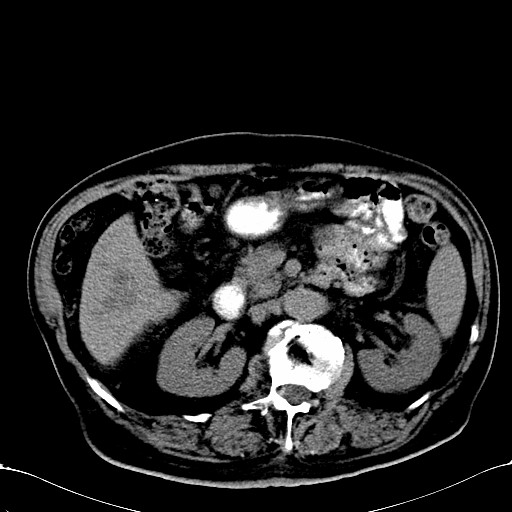

标题: CT28270:胰管扩张,肝多发占位 [打印本页]

标题: CT28270:胰管扩张,肝多发占位

患者,男,75岁。

肝脏多方低密度结节,边缘模糊,考虑多发转移,胰管明显扩张,建议增强扫描钩突情况

肝脏多发低密度灶,胰头似呈低密度,胰管扩张,建议增强,

胰管显著扩张,但胆总管未见扩张征象,不太符合胰头占位!考虑慢性胰腺炎.胃窦占位并肝内转移可能!mrcp胃镜增强一起上!